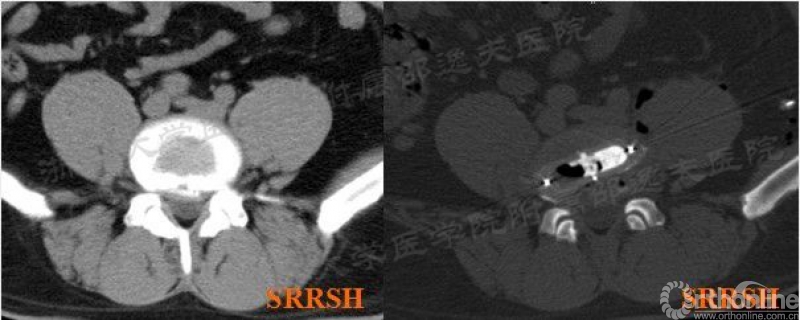

如果依照OLIF技术操作手册上用手指推开腹膜触摸的置针方法可能存在不小的安全隐患。而且一些特殊的病例,如腰大肌发达高耸(如图1),椎间盘被腰大肌完全覆盖,手指无法触摸清楚椎间盘结构位置,甚至部分腰大肌深部为主动脉等腹部重要结构,盲目导针定位穿刺根本无从下手且存在巨大风险;如一些椎间盘退变严重,椎间隙极度狭窄病例,加上周围骨赘增生,也无法手指触摸清楚椎间盘位置所在,非直视下穿刺定位不但无法找准椎间隙,而且容易损伤节段动脉等结构。

图1 L45节段不稳症,腰大肌高耸,通过AIP显露技术顺利完成手术